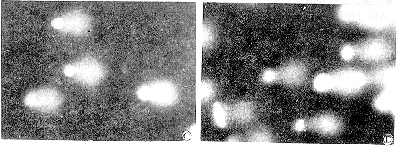

图1 CSS与CH单独或联合作用于HEL细胞后的SCGE图像

A:对照组; B:1.25×10-4支/毫升CSS; C:80 μg/ml CH; D:1.25×10-4支/毫升CSS+20 μg/ml CH

, 百拇医药 Fig 1 The comet image of HEL cells exposed to CSS and CH separately or simultaneously

A:control; B:1.25×10-4cig./ml CSS; C:80 μg/ml CH; D:1.25×10-4cig./ml CSS+20 μg/ml CH

1.CSS对HEL细胞DNA链断裂的影响:由表1和图1可见,对照组细胞电泳后产生的拖尾现象很不明显,而不同浓度的CSS与HEL细胞作用1小时后则可造成明显的拖尾现象。图像分析表明:不同浓度CSS作用后的尾部IOD与总IOD的比值均显著高于对照组。

2.CH对HEL细胞DNA链断裂的影响:由表2及图1可见,不同浓度的CH与HEL细胞作用1小时后也可造成明显的拖尾现象。图像分析表明:不同浓度的CH作用后的尾部IOD与总IOD的比值也均显著高于对照组。